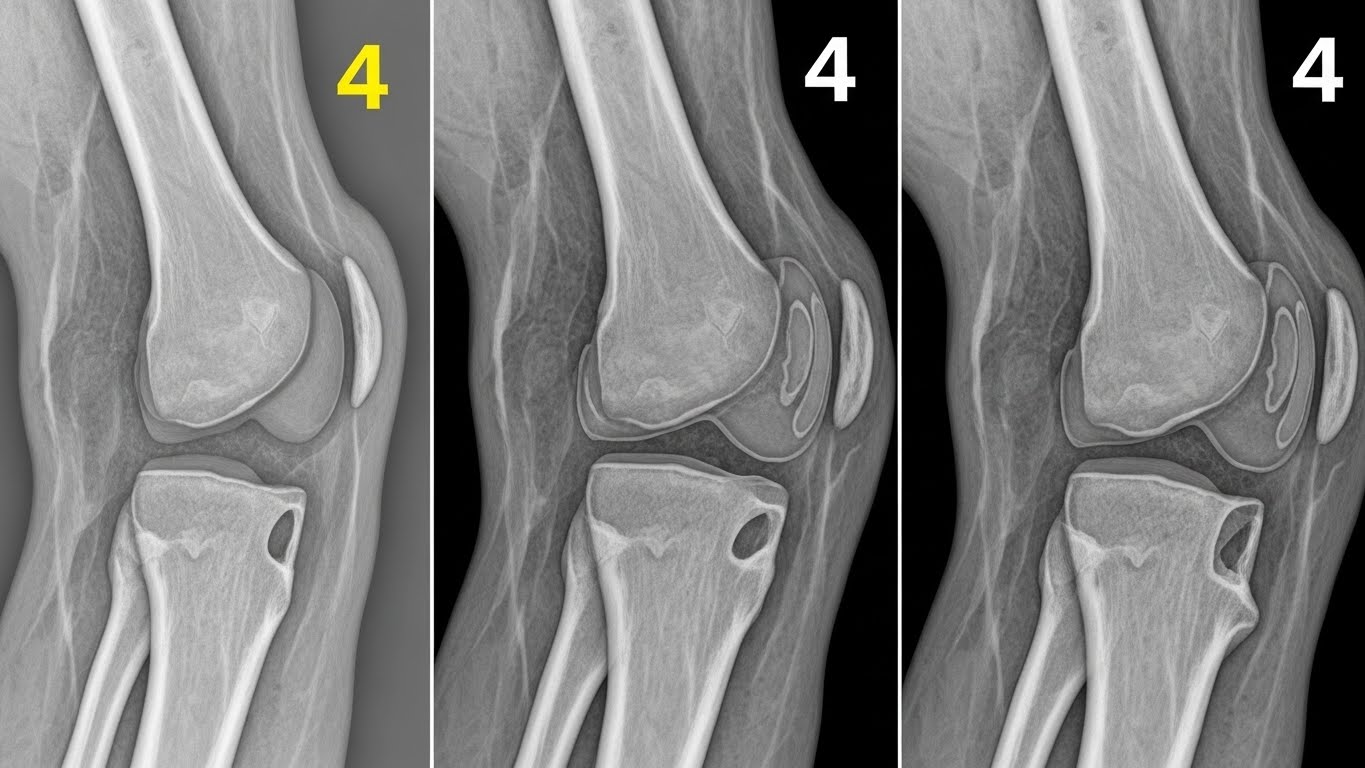

무릎 관절염은 진행 정도에 따라 1~4기로 나뉩니다. 통증이 심하다고 무조건 수술이 필요한 것은 아닙니다. 3기(중기)까지는 비수술 치료가 효과적입니다.

1기 (초기): 가끔 무릎이 시큰거리고 뻐근함. X-ray 상 연골 손상은 미미함.

2기 (초기~중기): 계단 오르내릴 때, 앉았다 일어설 때 통증 시작. 연골 손상이 시작되고 관절 간격이 약간 좁아짐.

3기 (중기): 통증이 만성화되어 휴식 중에도 느껴짐. O자형 다리 변형이 시작되거나 관절이 붓고 물이 차기 시작함. 인공관절 수술을 고려하는 시점.

4기 (말기): 연골이 완전히 닳아 뼈끼리 부딪히는 극심한 통증. 보행 장애 발생. 인공관절 수술이 불가피함.

만약 통증이 **2주 이상 지속**되고 무릎을 굽히고 펴는 데 어려움이 있다면, 2기 이상으로 진행되었을 가능성이 높습니다. [Image of osteoarthritis stages]